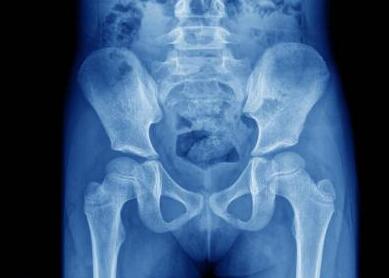

(图:X线下李先生膝关节示意图)

检查结果显示,李先生C-反应蛋白43.15mg/L,血沉120mm/L,RF和ANA均为阴性。膝关节遭受到严重的破坏,关节面边缘模糊不清,凹凸不平或囊状透亮区。